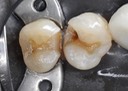

Joe Cha #20 finish